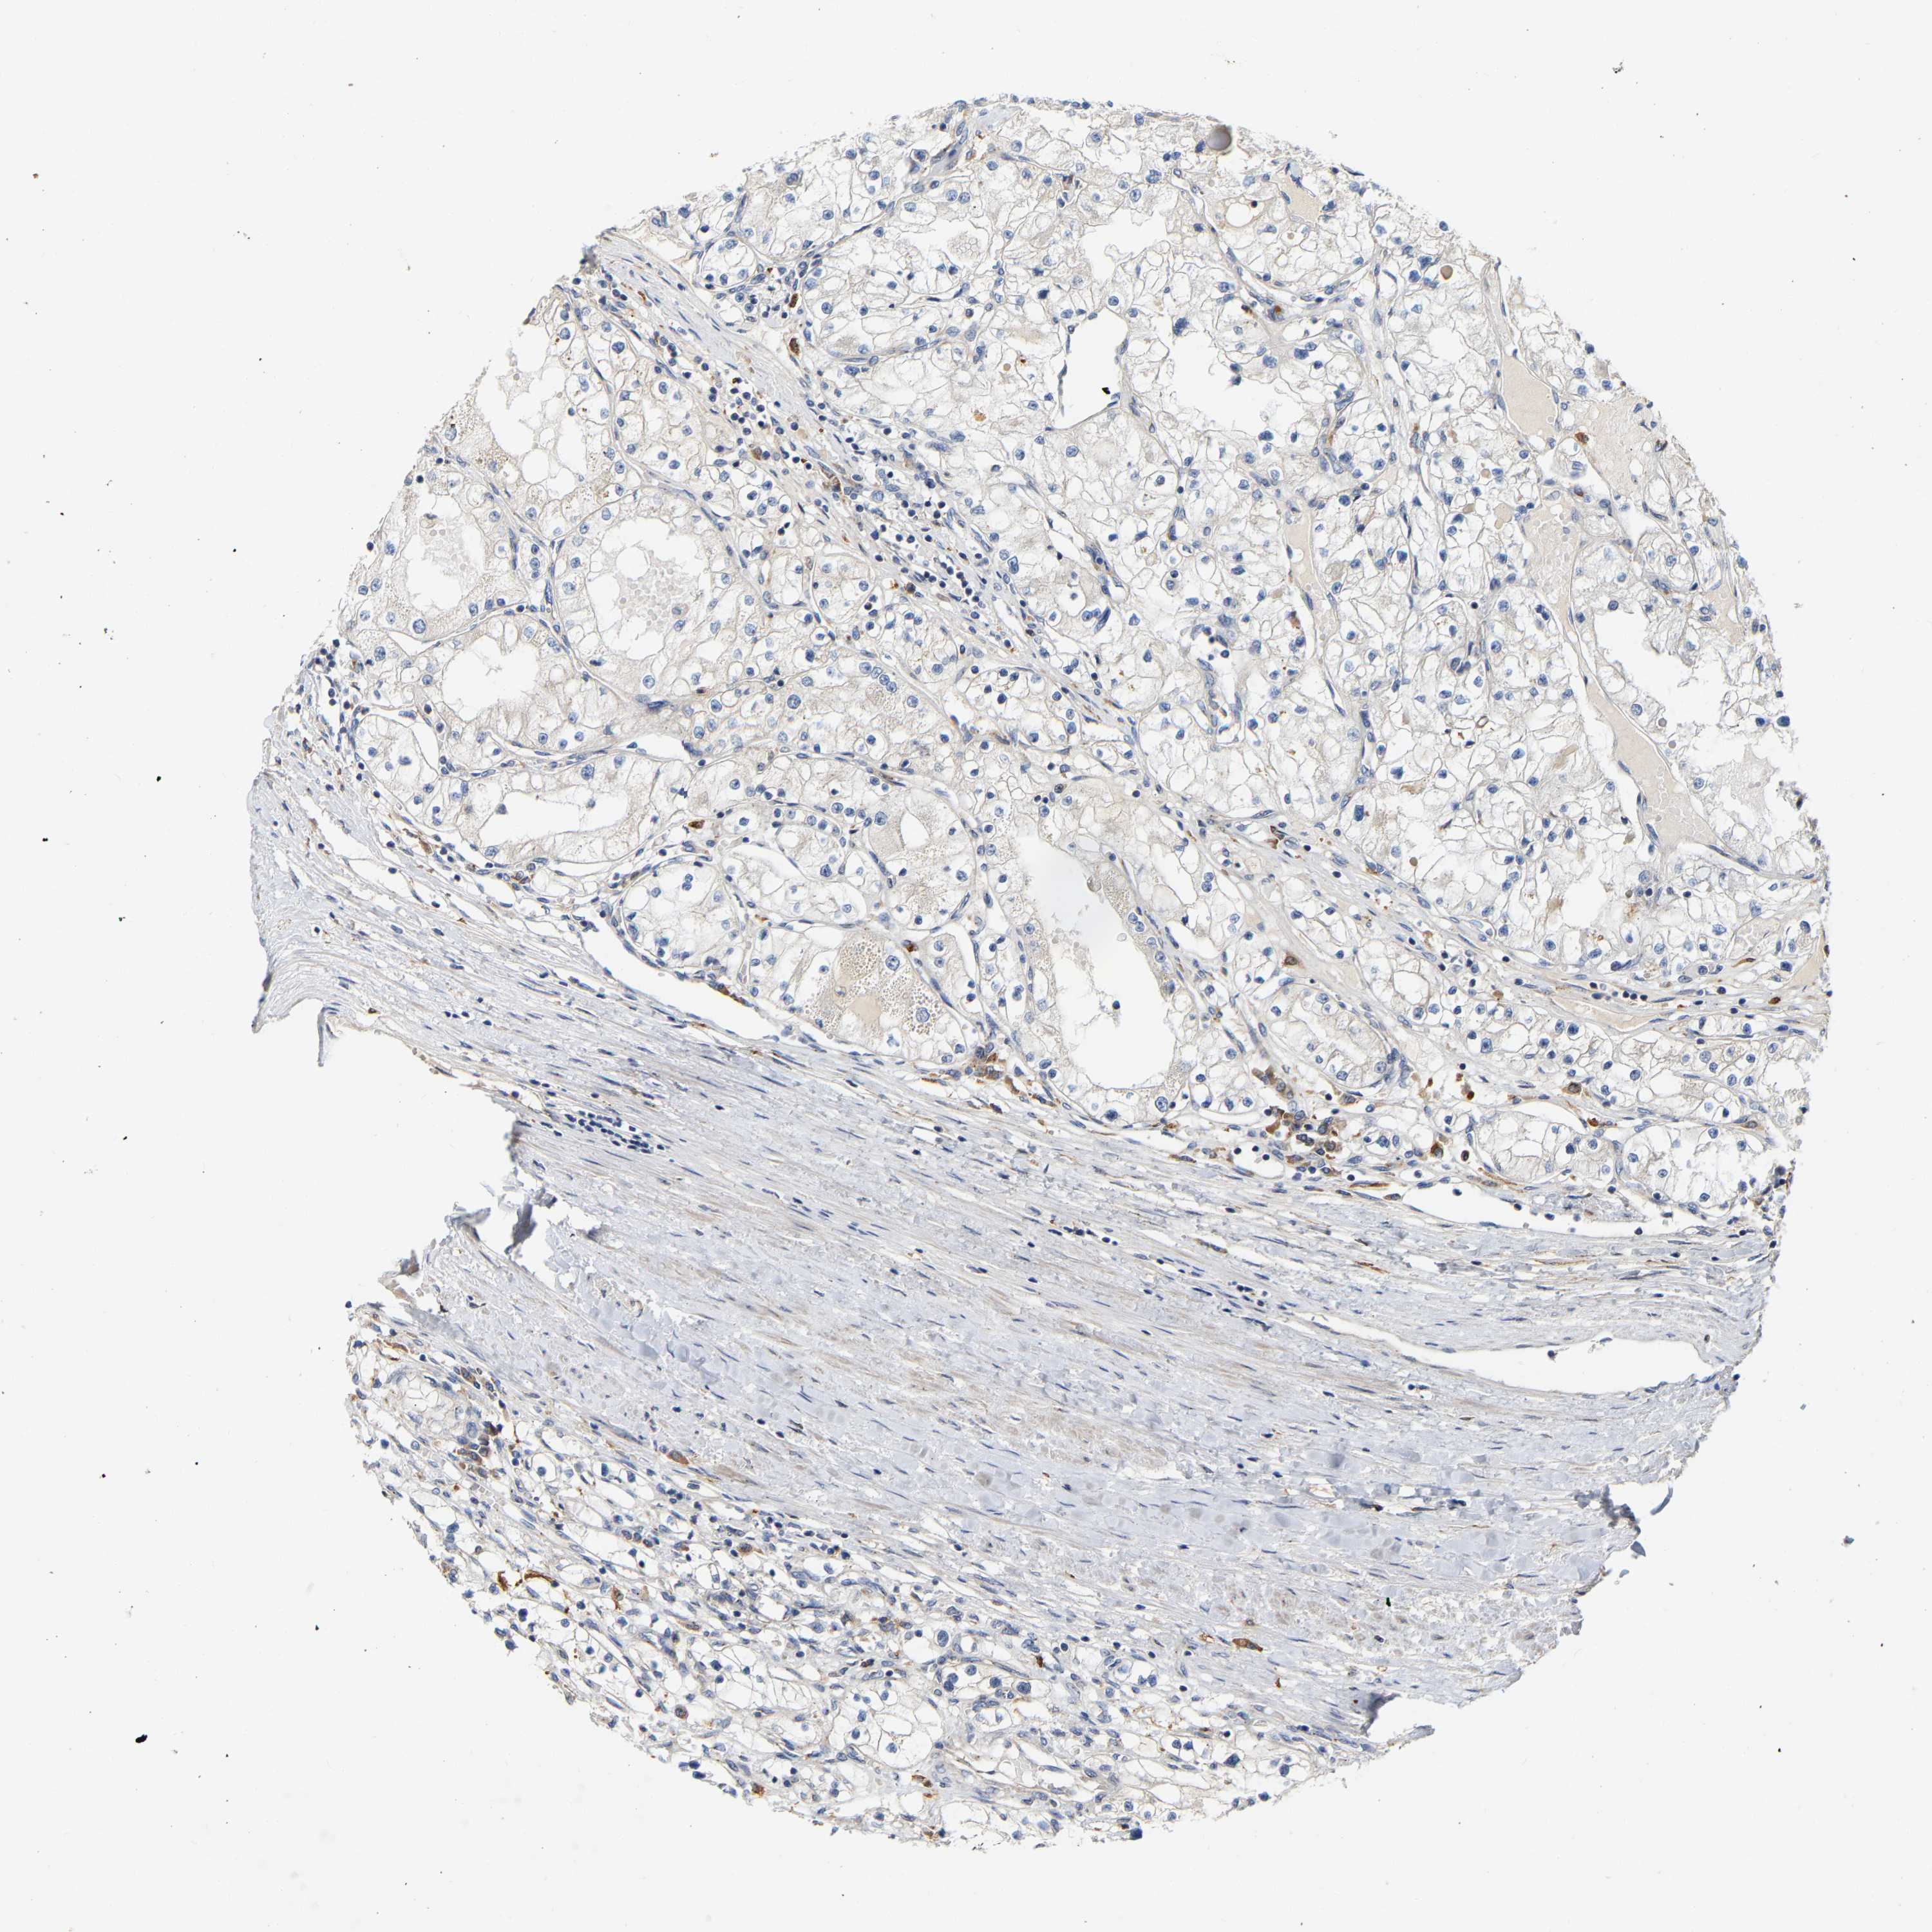

KIDNEY RENAL CLEAR CELL CARCINOMA (VALIDATION) - Interactive survival scatter ploti

The Survival Scatter plot shows the clinical status (i.e. dead or alive) for all individuals in the patient cohort, based on the same data that underlies the corresponding Kaplan-Meier plots. Patients that are alive at last time for follow-up are shown in blue and patients who have died during the study are shown in red.

The x-axis shows the expression levels (FPKM) of the investigated gene in the tumor tissue at the time of diagnosis. The y-axis shows the follow-up time after diagnosis (years). Both axes are complimented with kernel density curves demonstrating the data density over the axes. The top density plot shows the expression levels (FPKM) distribution among dead (red) and alive patients (blue). The right density plot shows the data density of the survived years of dead patients with high and low expression levels respectively, stratified using the cutoff indicated by the vertical dashed line through the Survival Scatter plot. This cutoff is automatically defined based on the FPKM cutoff that minimizes the p-score. The cutoff can be changed by dragging the vertical line or by entering a cutoff value in the square labeled "Current cut-off".

Under the Survival Scatter plot the p-score landscape (black curve; left axis) is shown together with dead median separation (red curve; right axis). Dead median separation is the difference in median mRNA expression between patients who have died with high and low expression, respectively. It is calculated as follows: median FPKM expression of dead patients with high expression - median FPKM expression of dead patients with low expression. This is intended to aid the user in visually exploring custom cutoffs and the associated p-scores and dead median separation.

Individual patient data is displayed and can be filtered by clicking on one or more of the category buttons on the top of the page. Categories describing expression level and patient information include: high, low, alive, dead, female, male and tumor stages. The scale of the x-axis can be toggled between linear and log-scale by clicking on the "x log" button. Mouse-over function shows TCGA ID, patient information and mRNA expression (FPKM) for each patient.

& Survival analysisi

Kaplan-Meier plots summarize results from analysis of correlation between mRNA expression level and patient survival. Patients were divided based on level of expression into one of the two groups "low" (under cut off) or "high" (over cut off). X-axis shows time for survival (years) and y-axis shows the probability of survival, where 1.0 corresponds to 100 percent.

PCNT is not prognostic in Kidney Renal Clear Cell Carcinoma (validation)

Best expression cut offi

Based on the FPKM value of each gene, patients were classified into two groups and association between prognosis (survival) and gene expression (FPKM) was examined. The best expression cut-off refers the FPKM value that yields maximal difference with regard to survival between the two groups at the lowest log-rank P-value. Best expression cut-off was selected based on survival analysis .

When clicking on this number, the vertical dashed line indicating cut-off, the interactive survival plot, and the Kaplan-Meier curve will be adjusted to show results based on the best expression cut-off.

: 5.35

P scorei

Log-rank P value for Kaplan-Meier plot showing results from analysis of correlation between mRNA expression level and patient survival.

N/A

TCGA RNA samplesi

RNA-seq data is reported as average FPKM (number Fragments Per Kilobase of exon per Million reads), generated by the The Cancer Genome Atlas (TCGA) .

Normal distribution across the dataset is visualized with box plots, shown as median and 25th and 75th percentiles. Points are displayed as outliers if they are above or below 1.5 times the interquartile range. FPKM values of the individual samples are presented next to the box plot.

Average pTPM 5.6

Number of samples 100